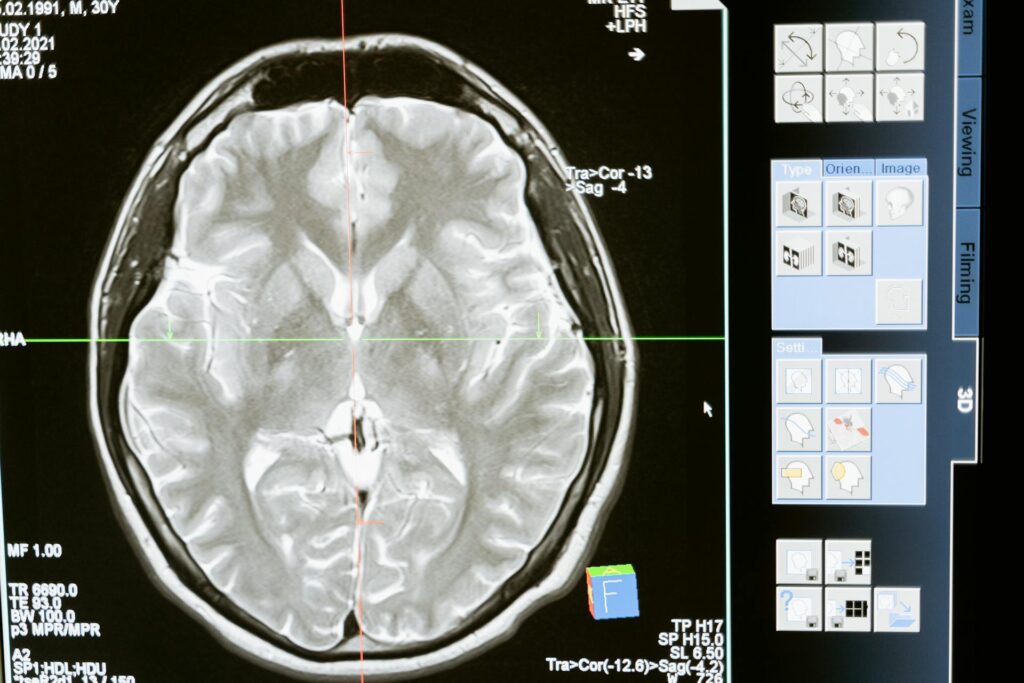

That part is the neocortex. It’s the famous wrinkled, gray outer layer that you see in any picture of a brain.

The scientific search for consciousness has long been “cortico-centric,” meaning it focuses on the neocortex. This is the part of our brain that is newest in evolutionary terms.

- The Cortex: The new, wrinkled outer layer.

Coppola looked at what happens when you alter or damage each part. The results paint a picture that is completely upside-down from the traditional view.

Stimulating the cortex does, in fact, change your experience. It can make you hallucinate or change your sense of self.